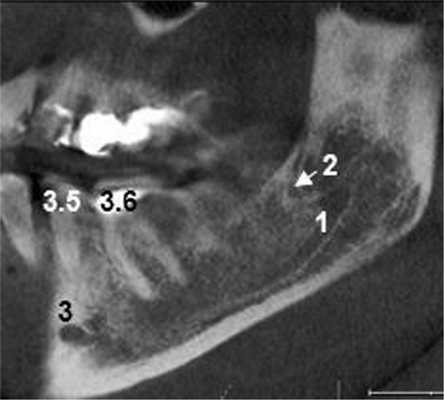

Ниже представлены описания рентгенологической картины раздвоенного канала НЧ 3 типов.

Пациентка Е., 48 лет. С левой стороны на уровне угла НЧ от нижнечелюстного канала отходила боковая ветвь (рис. 2). Рис. 2. Ретромолярный канал; КЛКТ пациентки Е., 48 лет. 1 — канал НЧ; 2 — ретромолярный канал; 3 — подбородочное отверстие. Ее поперечный диаметр составлял 1,37 мм у места начала и 0,96 мм в области ретромолярного отверстия.

Поперечный диаметр канала НЧ у места начала ветви — 3,08 мм. Сначала дополнительный канал направлялся вперед. На расстоянии 5,33 мм от места бифуркации он образовывал петлю, менял направления хода и шел назад и вверх, заканчиваясь отверстием в ретромолярной области. Описанный ход характерен для ретромолярного канала (4-й тип раздвоенного канала НЧ). На контралатеральной стороне дополнительных каналов НЧ не обнаружено.

По данным литературы, чаще всего встречаются 4-й и 1-й типы раздвоенного канала Н.Ч. Среди прочих вариантов анатомического строения канала они были обнаружены соответственно в 52,5—71,3 и 18,8—44,3% случаев [4—7]. Щечно-язычный и дентальный тип канала выявлялись в 0,5—8,3% наблюдений. В общей популяции, по данным L. Haas и соавт. [8], на ОПМГ и КЛКТ-сканах частота встречаемости ретромолярного канала составляет 4,20%, а всех других типов раздвоенного канала — 16,25%.